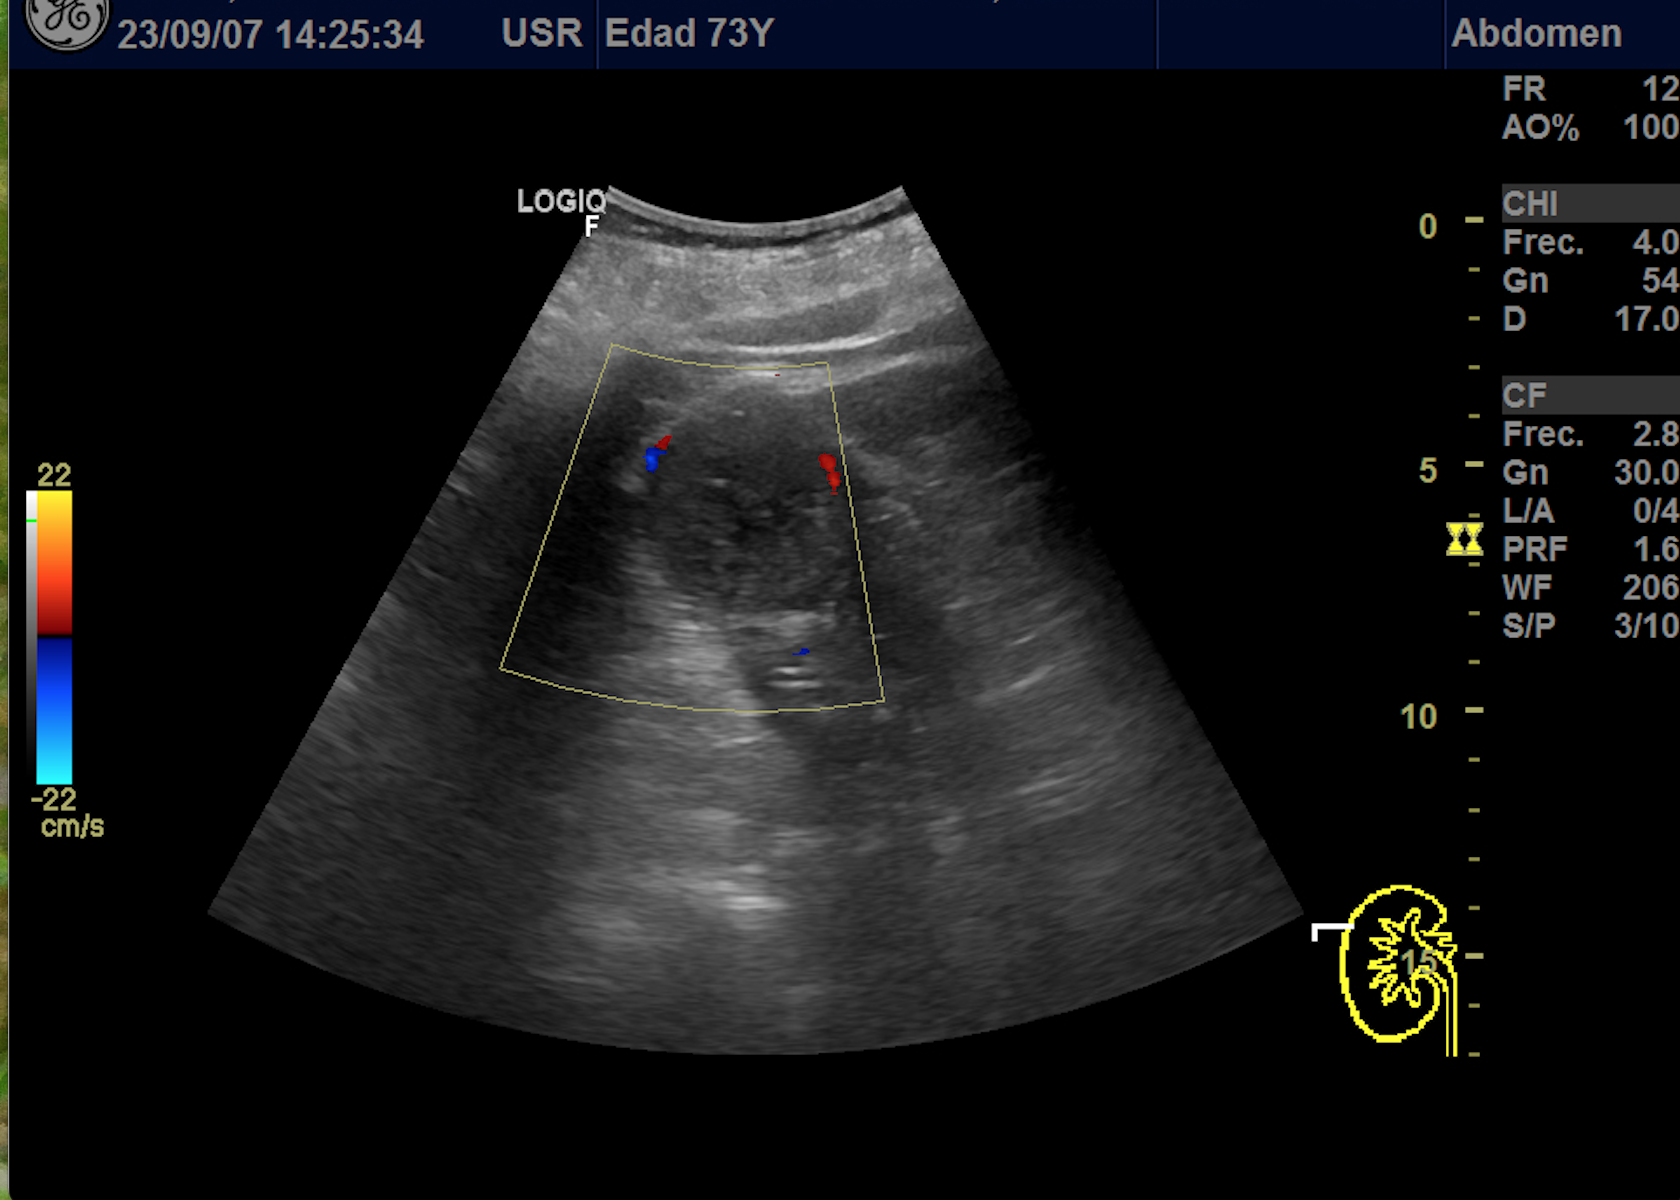

Hallazgos ecográficos

En polo superior de riñón derecho se observa una imagen redondeada, bien delimitada, isoecoica con un área central hipoecoica con vascularización periférica y central de 4,1 x 4,18 x 4,94 cm.

Dado el hallazgo de una masa renal se deriva a urología por el circuito de sospecha de malignidad.